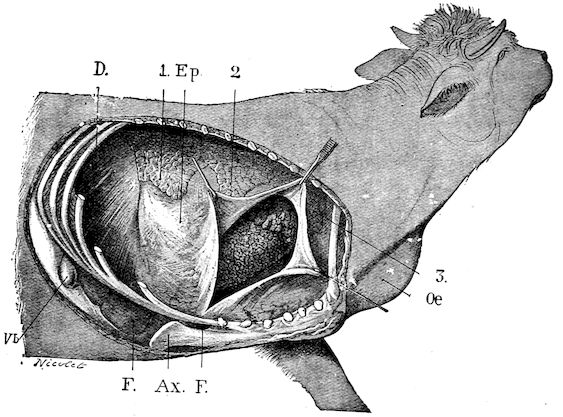

Fig. 1.—Rachitis in a young goat.

Fig. 1.—Rachitis in a young goat.